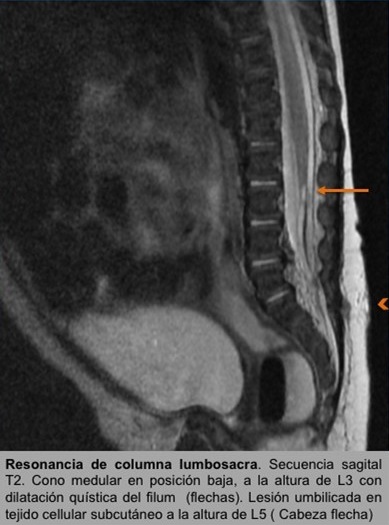

• RM de columna lumbosacra: hallazgos compatibles con disrafismo espinal oculto, seno dérmico con obliteración fibrosa de la comunicación con canal vertebral en paciente con médula anclada (cono medular a la altura de cuerpo vertebral L3) que asocia dilatación quística del filum terminal y lipomatosis.